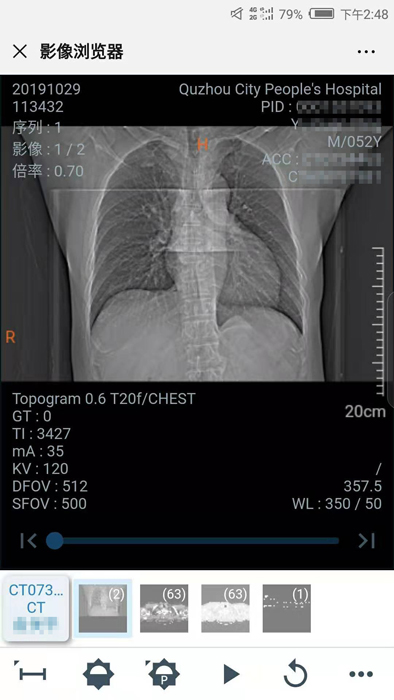

10月29日晚,我院向住院患者推行數(shù)字影像服務(wù),云膠片正式上線!點(diǎn)點(diǎn)手機(jī)就能查看片子不限次數(shù)瀏覽影像……方便、省錢、精準(zhǔn)、環(huán)保,“云影像”服務(wù)平臺(tái)讓您看病更省心。

“影像圖片十分清晰,還能根據(jù)自己的需求放大縮小,這可比拿著膠片到處跑省心多了!”

10月30日,住院患者俞先生收到一條短信提醒“【云影像】衢州市人民醫(yī)院提醒您,俞先生的CT報(bào)告已完成……”俞先生隨即點(diǎn)擊手機(jī)上的瀏覽鏈接,輸入身份證后六位,驗(yàn)證完成,短短幾秒鐘,躺在病床上也能查看到自己的CT電子報(bào)告和影像,俞先生直呼神奇。

“醫(yī)院面向住院患者全面推行檢查檢驗(yàn)結(jié)果電子化,互認(rèn)共享,全面提供網(wǎng)上查詢、移動(dòng)推送等服務(wù),‘云影像’平臺(tái)的運(yùn)行就是深化‘最多跑一次’改革要求的又一新舉措?!贬t(yī)院信息處工作人員介紹,“ ‘云影像’是儲(chǔ)存在云端的病人醫(yī)學(xué)影像檢查信息,包括檢查報(bào)告、電子膠片及供專業(yè)影像科醫(yī)生診斷瀏覽的全部醫(yī)學(xué)數(shù)字原始影像。放射檢查報(bào)告完成后,醫(yī)院會(huì)同步發(fā)送提醒短信到患者的手機(jī)上,只要點(diǎn)擊短信上的鏈接就可第一時(shí)間獲取‘云影像’及報(bào)告。使用‘云影像’查看檢查報(bào)告,解決了排隊(duì)取片、復(fù)診帶片的煩惱,縮短了就醫(yī)時(shí)間,讓老百姓看病得到實(shí)實(shí)在在的方便。”